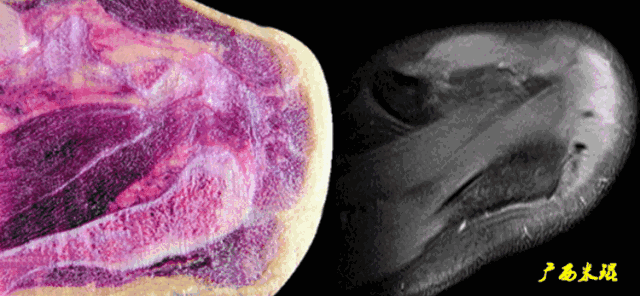

肩袖撕裂分裂

按照损伤程度分为部分撕裂( MR准确性>85% )和完全撕裂(MR准确性>95% )。部分撕裂按照受损部位又分为滑囊面、关节面及肌腱内撕裂,在MRI上可以清晰的看到其受损部位。

肩袖撕裂的MRI表现

(1)信号异常

肩袖出现3级信号,是诊断的直接征象,一旦发现3级信号,肩袖撕裂无疑。

a.肩袖关节侧出现3级信号,部分撕裂。

b.肩袖滑囊侧出现3级信号,属于部分撕裂。

c.肩袖内部出现大范围3级信号,属于部分撕裂。

d.肩袖出现3级信号,关节侧撕裂回缩,也属于部分撕裂。

e.肩袖出现3级信号,肩袖完全中断,属于完全撕裂但无回缩。